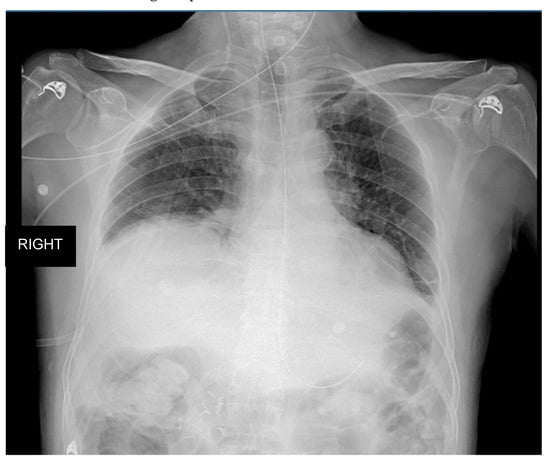

3.2. Clinical Case Two